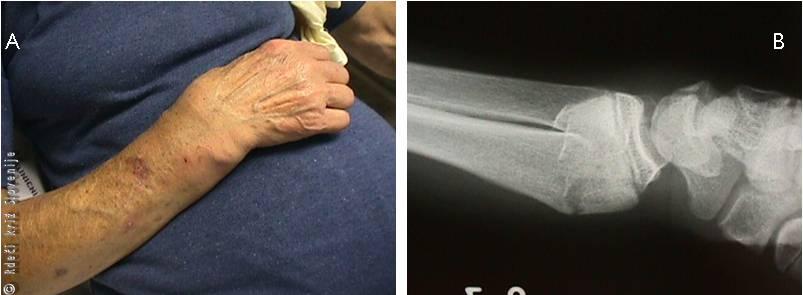

Slika 18

A – Zlom koželjnice na tipičnem mestu pri starostniku. Prisotni sta značilna bajonetno spremenjena oblika in oteklina v predelu zapestja.

B – Prednja in stranska rentgenska slika zapestja po zlomu koželjnice na tipičnem mestu. Na stranskem posnetku je viden premik odlomka navzad, kar se navzven kaže z bajonetno spremembo oblike.